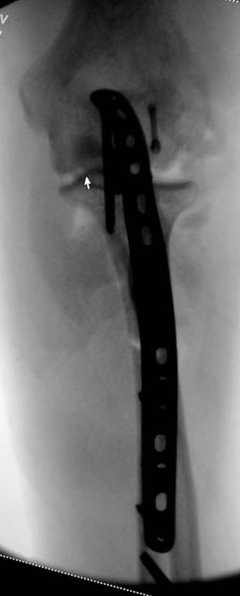

Для фиксации перелома локтевого отростка на сегодня множество преконтурных с блокирующими возможностями пластин.

Стабильную фиксацию, особенно при оскольчатых

переломах, можно добиться, применяя технику Bridge Plate, и за счет тех пластин, где имеется возможность проведения множественных шурупов (2.7 мм) проксимально.

Здесь выставлены несколько случаев и варианты фиксации локтевого отростка, некоторые в комбинации с другими переломами.

3 вариант

перелом с capitelum humerus и проксимальной трети улна